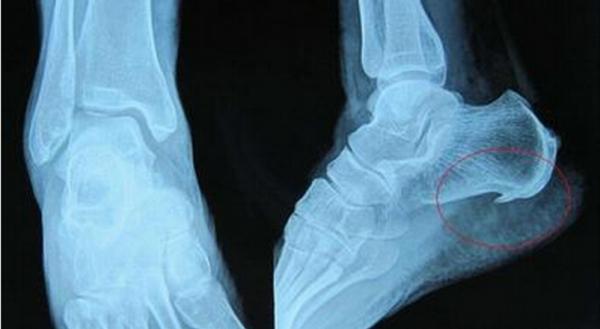

足跟骨刺也很常見

骨刺也叫骨質增生,多發於上了歲數的人群,理論上來講骨刺更容易出現在身體的各個關節部位。只要骨刺壓迫到了附近的神經組織就會出現疼痛,相信有不少中老年人都經歷過那種尖銳的痛感。

足跟出現骨刺之後附近的面板會有明顯的痛感,類似於石頭硌腳或者是尖銳物體刺腳,只要走路就會加重痛感。這種情況還是儘早就醫,採取正確的方法應對才能減少痛苦。